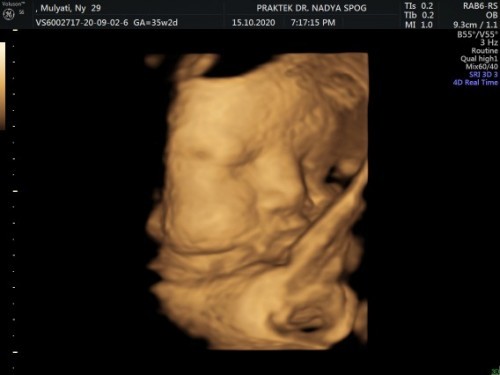

Waktu kandungan 35minggu🥰 dan tiap diusg selalu kaga mau dan manyun” 😘🤣